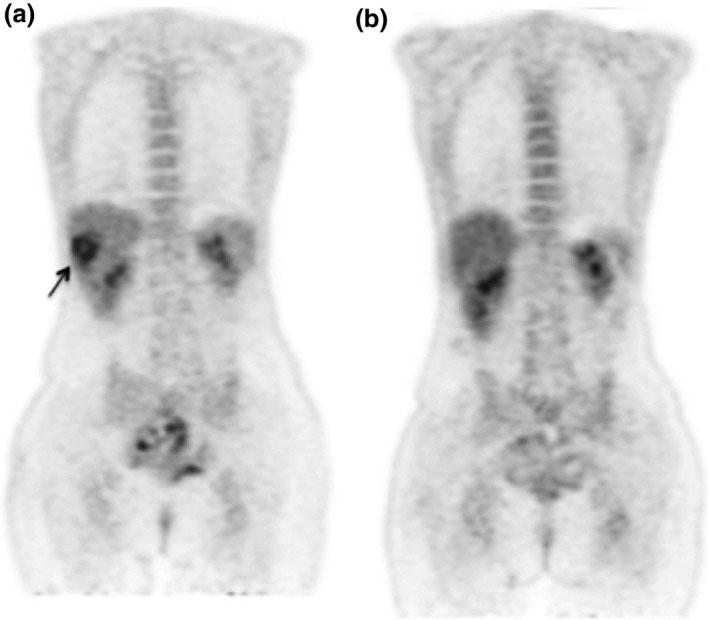

Esta dependencia de la atención médica en los tratamientos sistémicos es en parte por el modo en que se identifican los tumores metastásicos. En general, se usan técnicas de obtención de imágenes, como las tomografías por emisión de positrones (TEP) y las tomografías computarizadas (TC).

“Nos limita la capacidad de obtener imágenes precisas de las metástasis”, indicó el doctor Vikram. Agregó que, “cada año, [las técnicas] parecen mejorar”. Sin embargo, incluso con los métodos más innovadores hay limitaciones y no siempre es posible descartar la presencia de micrometástasis (unas pocas células tumorales que se diseminan desde el tumor primario), que se esconden en los pulmones, el encéfalo o los huesos.